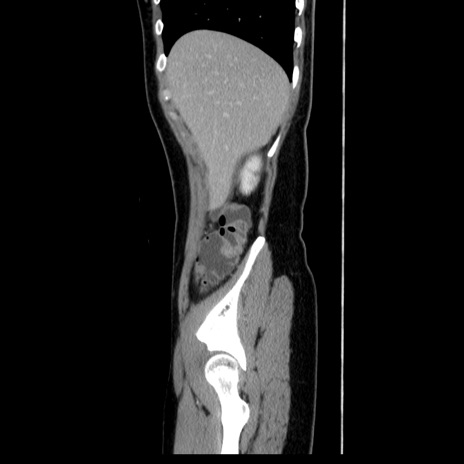

症例39(矢状断像)

【症例】40歳代女性

【主訴】上下腹部痛

【現病歴】2日目から下腹部痛あり。夜間は痛みで眠れなかった。昨日より上腹部痛と下痢が出現。臥位で痛みは軽快したため、休んでいた。本日になって臥位でも立位でも痛みが強くなってきたため救急要請。

【既往歴】子宮内膜症

【身体所見】部:平坦・軟、左上下腹部に圧痛あり、反跳痛あり。

【データ】WBC 21800、CRP 26.78

CT